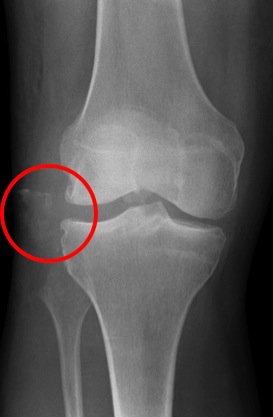

Fibula head avulsion / dislocation

Will typically have LCL and biceps femoris ligament attached

Fibular head avulsion

Fibula head avulsion and medial tibial plateau fracture